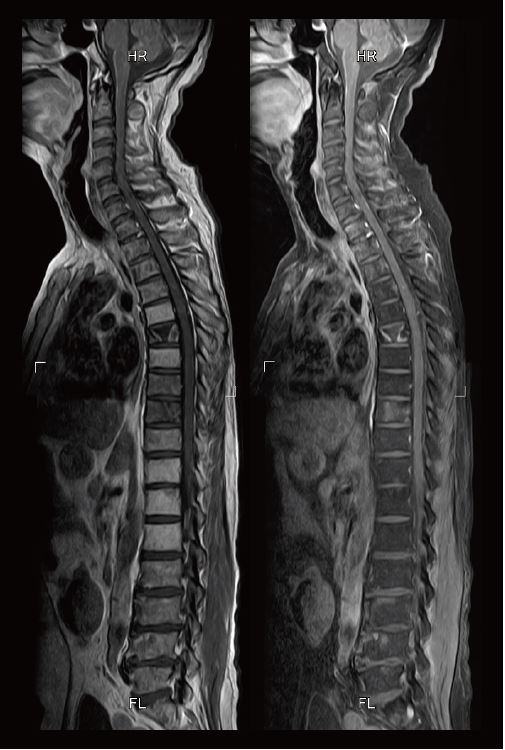

На рис. 1 наведено клінічний випадок карциноматозного менінгіту та кісткових метастазів первинного раку легень. Таким пацієнтам необхідно періодично проходити МРТ всього хребта, але вони можуть відчувати дискомфорт через тривалість обстеження. Раніше для отримання двох типів зображень (T1-зважених зображень і T1-зважених зображень з придушенням жиру) загальний час дослідження становив приблизно 15 хвилин.

З іншого боку, коли використовується WFS DIXON, T1-зважені зображення та T1-зважені зображення придушення жиру можна отримати за одне сканування, що призводить до значного скорочення часу обстеження. Переваги меншого часу обстеження в контрастній візуалізації всього хребта (яка, як правило, займає відносно багато часу) полягають у значному зниженні навантаження на пацієнта, а також скороченні часу перебування в екзаменаційній кімнаті.

Рис.1. Т1-зважене зображення всього хребта зроблене за допомогою WFS DIXON. Зліва: зображення у фазі. Праворуч: зображення води. Під час одного сканування всього хребта можна отримати два типи зображень, що скорочує час обстеження.